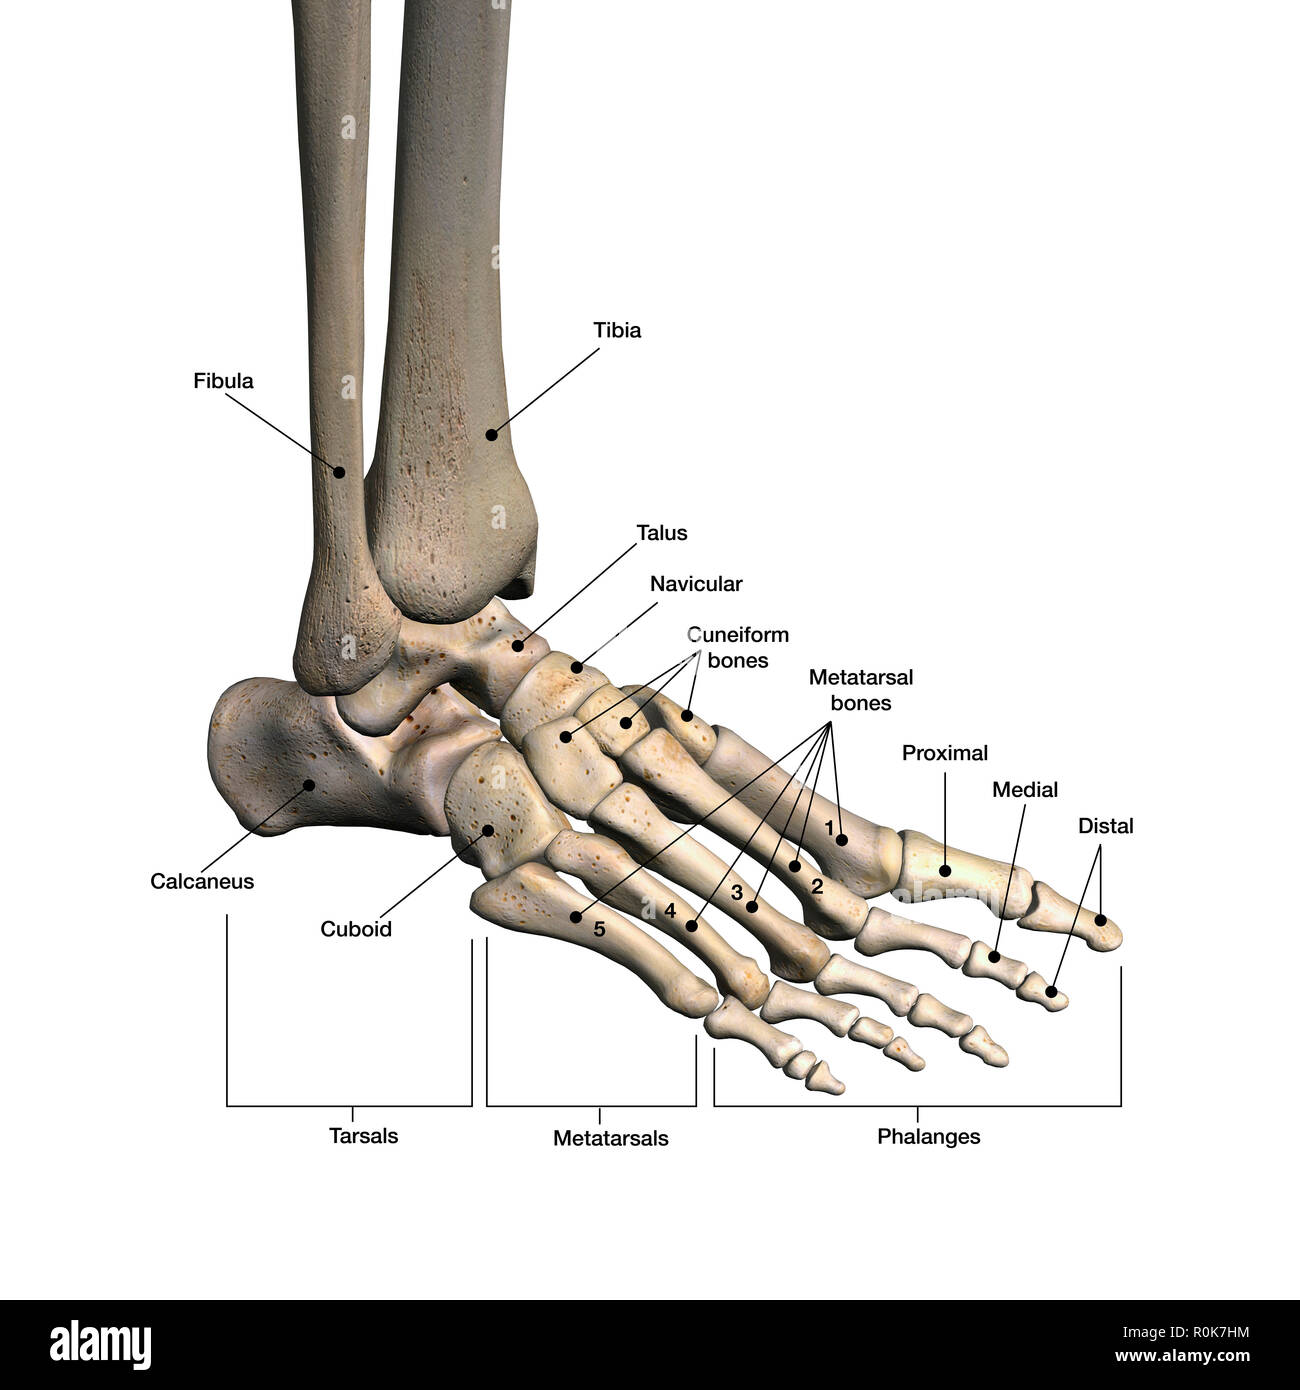

anatomia dei piedi Piede ossa knochen foot beschriftet fusses contrassegnate calcaneus phalanges fersenbein tarsals fußes anatomy

Strukturelle Anatomie Menschlicher Fußknochen — Computer

Bones Of The Foot, Labeled Royalty Free Stock Photo - Image: 8616465

www.dreamstime.compiede ossa knochen foot beschriftet fusses contrassegnate calcaneus phalanges fersenbein tarsals fußes anatomy

www.dreamstime.compiede ossa knochen foot beschriftet fusses contrassegnate calcaneus phalanges fersenbein tarsals fußes anatomy